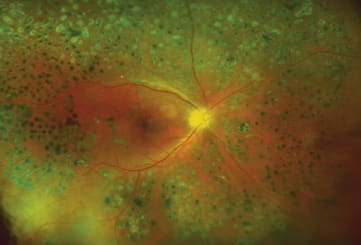

Figure 1. A dilated fundus exam led to a diagnosis of quiescent PDR after treatment with PRP laser.

Figure 2. UWFFA revealed extensive areas of peripheral ischemia and active neovascularization that was not detected on the dilated fundus exam.